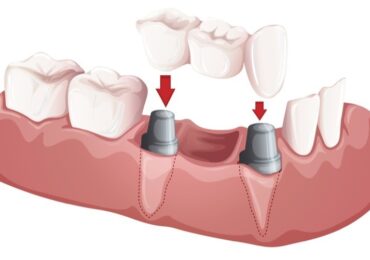

Implants

We offer state-of-the art implants designed to be strong as well as beautiful.